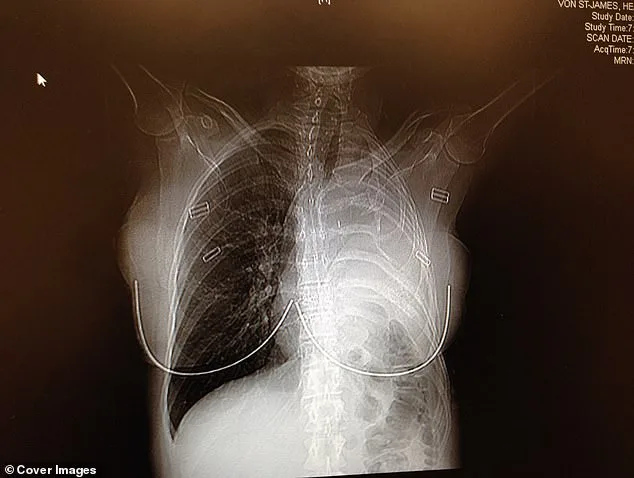

In February 2006, doctors performed a radical surgery that would redefine her existence. They removed her left lung, the rib above it, the lining of her heart, and part of her diaphragm. In their place, they used surgical Gore-Tex—the same material found in waterproof clothing—to rebuild parts of her chest. "The tumor was excised with clean margins," her surgeon noted. "No visible cancer remained." As an additional precaution, doctors infused warm drugs directly into her chest cavity, rocking her back and forth for an hour to circulate the medicine and kill any remaining cancer cells. "Patients call it the 'shake and bake,'" Von St James said, her voice tinged with both humor and exhaustion.